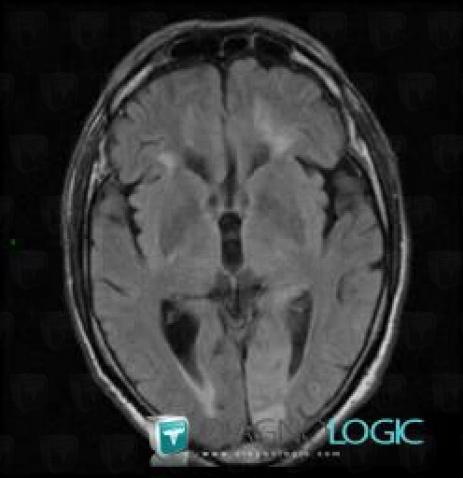

Cerebral infarction, Cortico subcortical region, Cerebral hemispheres, MRI

Here is the specific information in the key image above:

- Diagnosis Cerebral infarction, Location(s) Cortico subcortical region, with gamuts Cortical lesion, Subcortical lesionCerebral hemispheres, with gamuts Intracerebral T2W or FLAIR hyperintense lesion, Parietal posterior or occipital T2WI or FLAIR hyperintense lesion